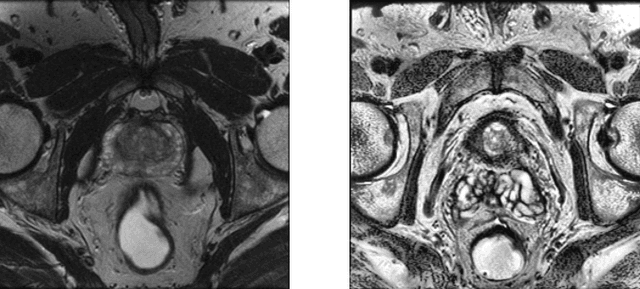

Abstract:Prostate cancer (PCa) is the second most common cancer diagnosed among men worldwide. The current PCa diagnostic pathway comes at the cost of substantial overdiagnosis, leading to unnecessary treatment and further testing. Bi-parametric magnetic resonance imaging (bp-MRI) based on apparent diffusion coefficient maps (ADC) and T2-weighted (T2w) sequences has been proposed as a triage test to differentiate between clinically significant (cS) and non-clinically significant (ncS) prostate lesions. However, analysis of the sequences relies on expertise, requires specialized training, and suffers from inter-observer variability. Deep learning (DL) techniques hold promise in tasks such as classification and detection. Nevertheless, they rely on large amounts of annotated data which is not common in the medical field. In order to palliate such issues, existing works rely on transfer learning (TL) and ImageNet pre-training, which has been proven to be sub-optimal for the medical imaging domain. In this paper, we present a patch-based pre-training strategy to distinguish between cS and ncS lesions which exploit the region of interest (ROI) of the patched source domain to efficiently train a classifier in the full-slice target domain which does not require annotations by making use of transfer learning (TL). We provide a comprehensive comparison between several CNNs architectures and different settings which are presented as a baseline. Moreover, we explore cross-domain TL which exploits both MRI modalities and improves single modality results. Finally, we show how our approaches outperform the standard approaches by a considerable margin

Abstract:Traditional deep learning (DL) approaches based on supervised learning paradigms require large amounts of annotated data that are rarely available in the medical domain. Unsupervised Out-of-distribution (OOD) detection is an alternative that requires less annotated data. Further, OOD applications exploit the class skewness commonly present in medical data. Magnetic resonance imaging (MRI) has proven to be useful for prostate cancer (PCa) diagnosis and management, but current DL approaches rely on T2w axial MRI, which suffers from low out-of-plane resolution. We propose a multi-stream approach to accommodate different T2w directions to improve the performance of PCa lesion detection in an OOD approach. We evaluate our approach on a publicly available data-set, obtaining better detection results in terms of AUC when compared to a single direction approach (73.1 vs 82.3). Our results show the potential of OOD approaches for PCa lesion detection based on MRI.